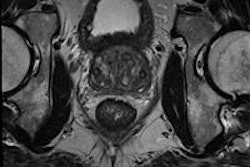

Articles in the latest issue (BJR, April 2014, Vol. 87:1036) include overviews of topics such as postmortem MRI as an alternative for nonforensic autopsy in fetuses and children, adult postmortem imaging in traumatic and cardiorespiratory death and its relation to clinical radiological imaging, and advances in postmortem CT angiography. An original article from Swiss authors focuses on identifying methamphetamine drug mules using digital radiography.